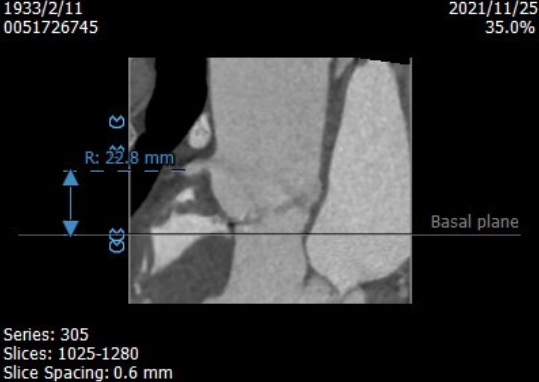

术前CT评估:

Annulus 22.8*27.8mm Perimeter=78.4mm

左冠高度15.1mm

右冠高度22.8mm